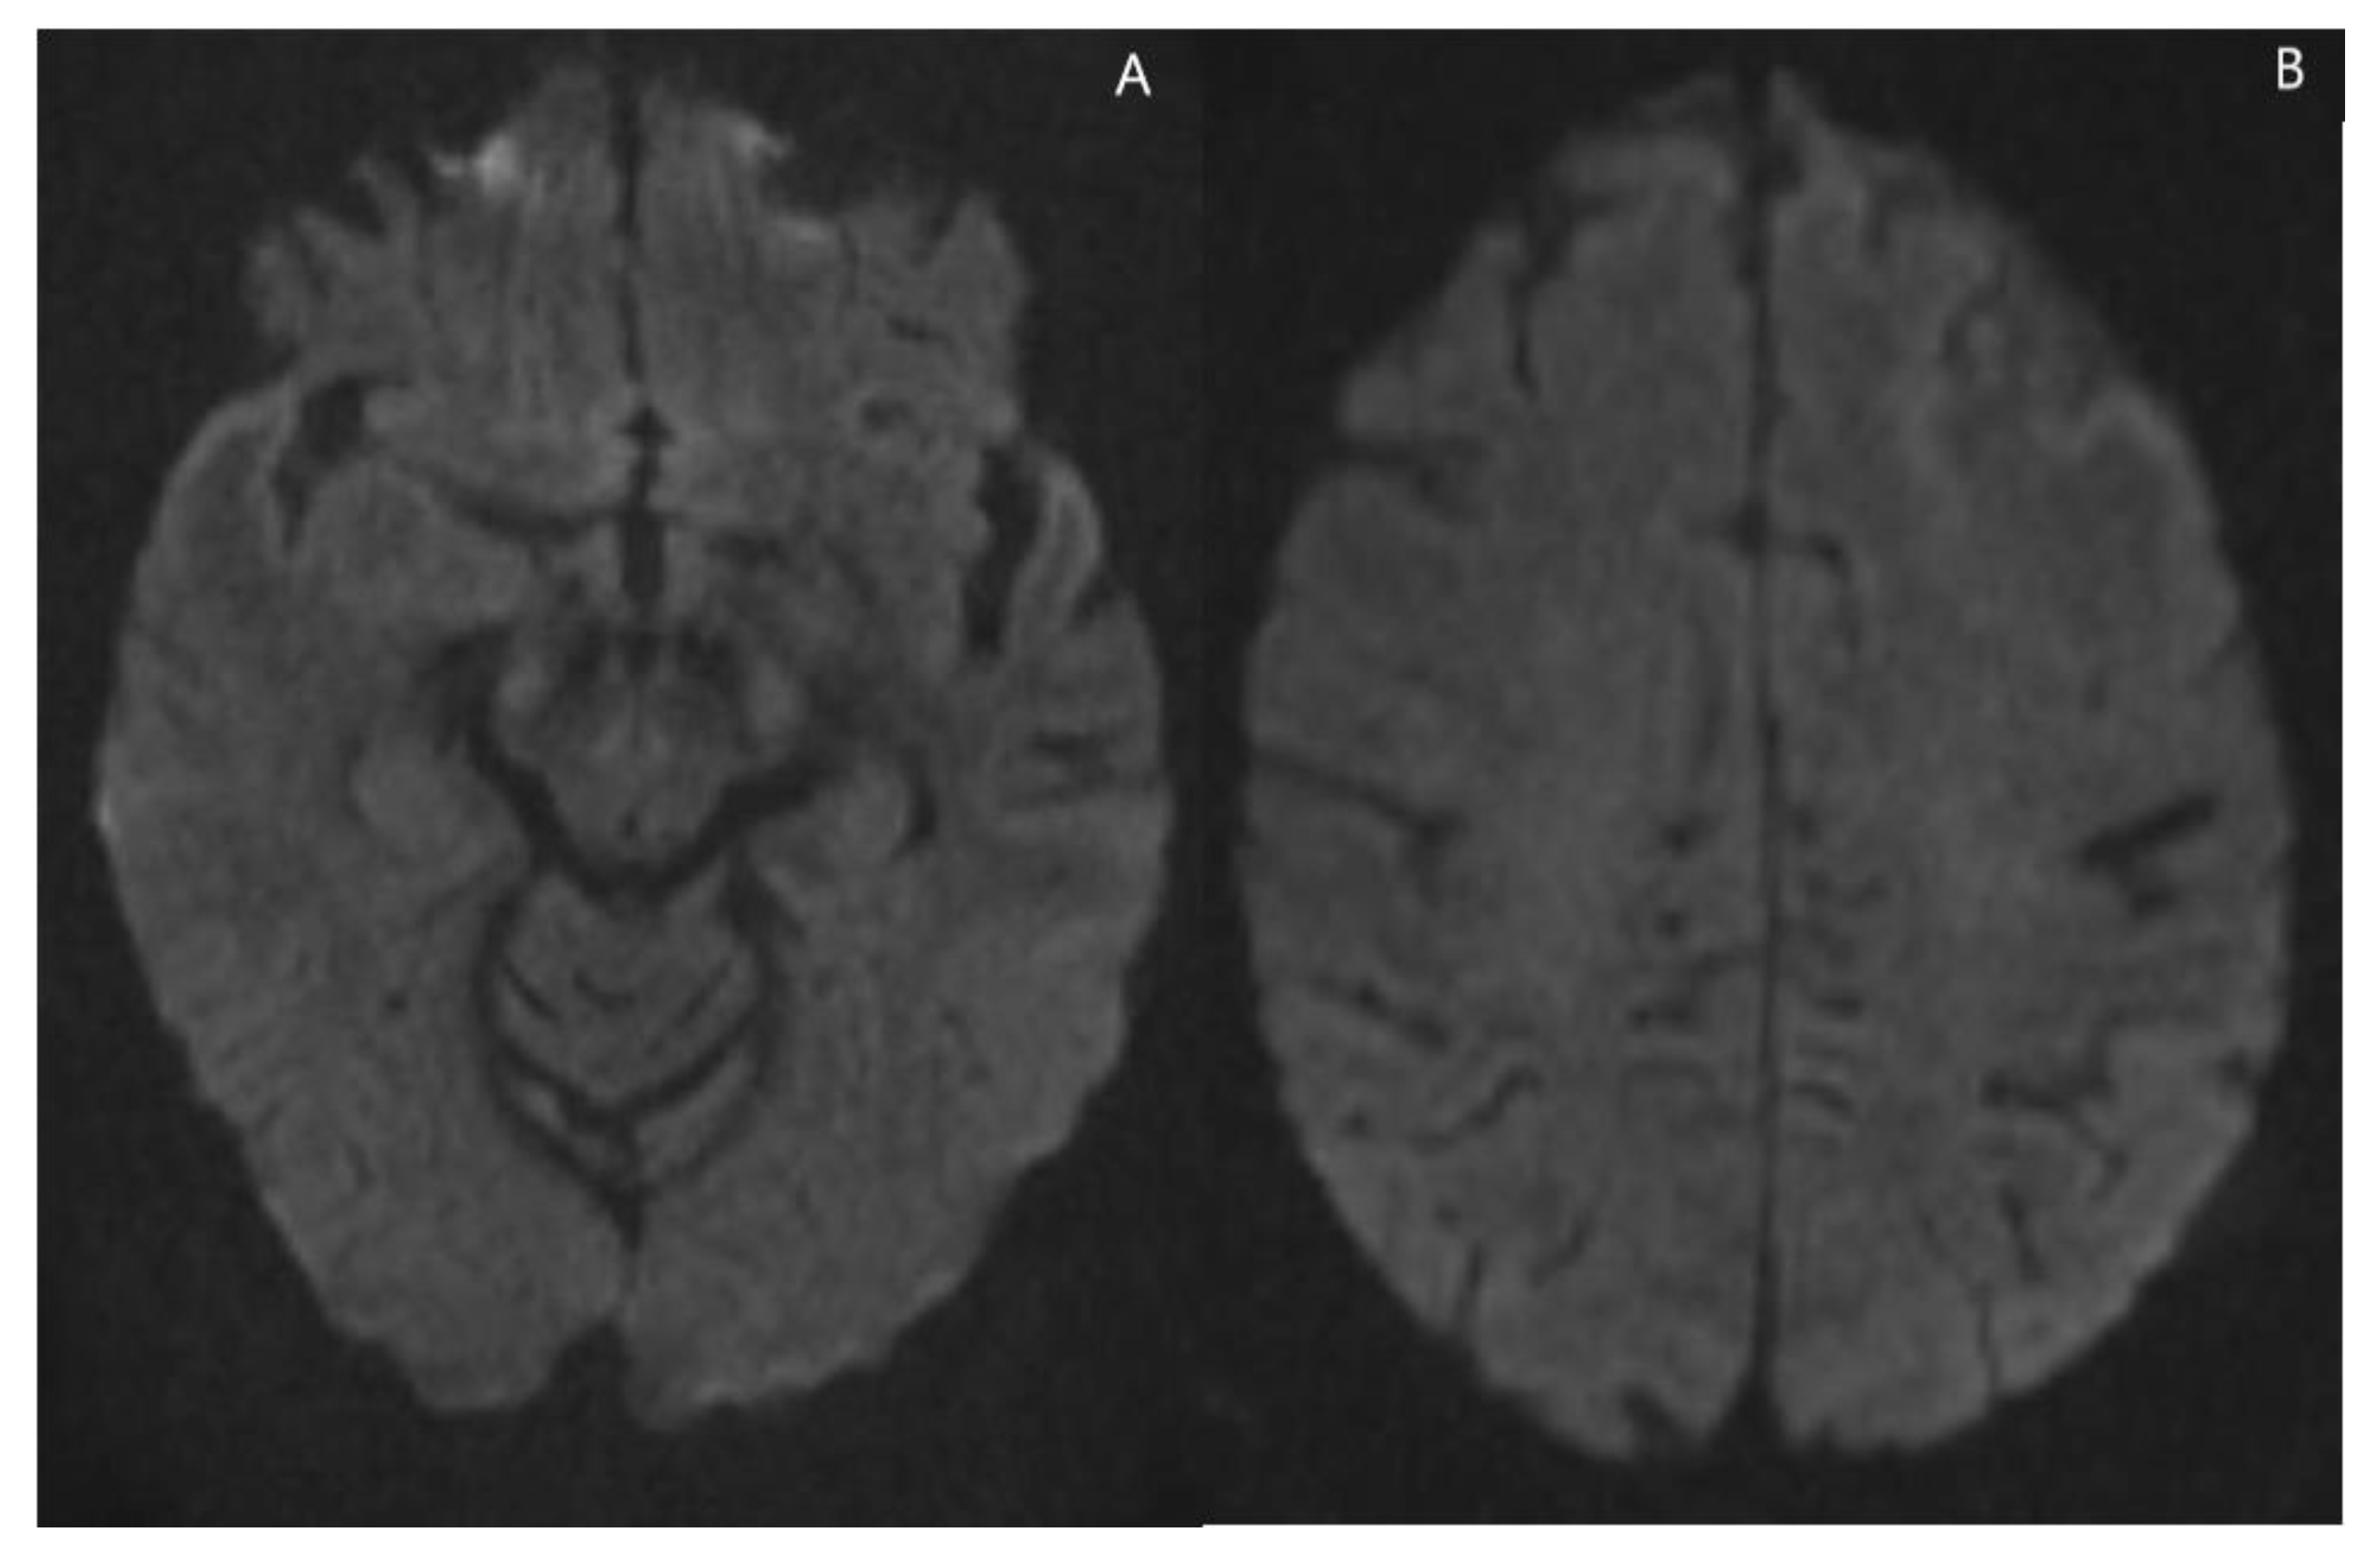

2. Case Presentation

| Apparent Diffusion Coefficient (ADC) elevated with areas of restricted diffusion. Susceptibility weighted imaging shows a peripheral pattern of punctate hypo intensities |